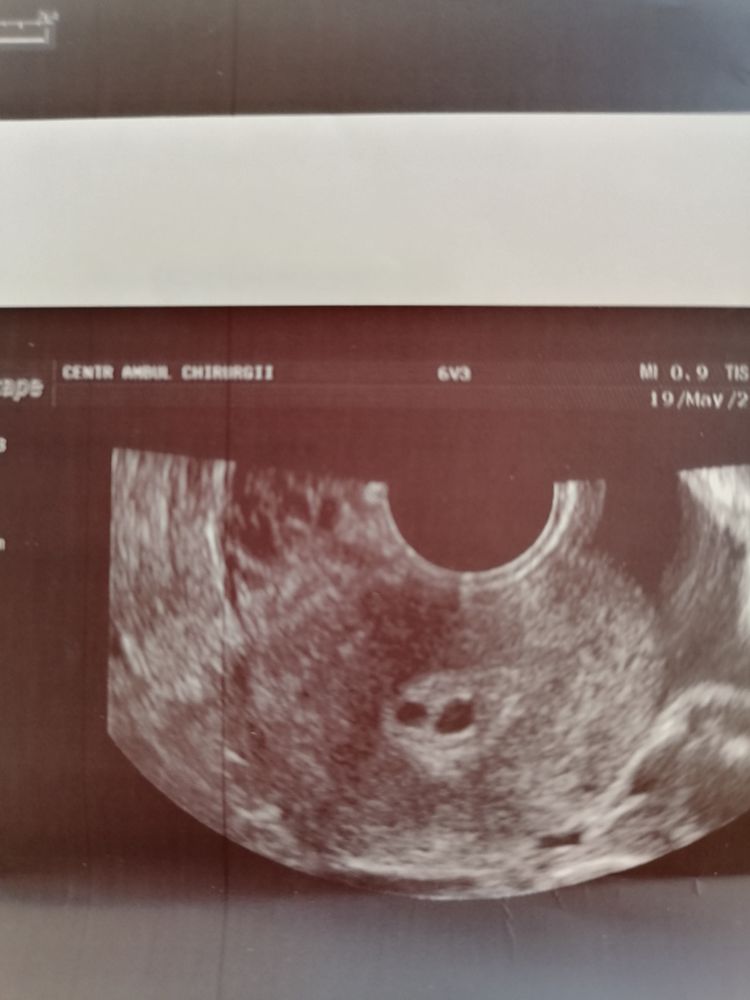

Ложусь на УЗИ, а врач "а мы что, двоих переносили?". В итоге 2 "ДВА" плодных яйца. Одно побольше с желточный мешочком, другое меньше и без него. Я в шоке, прострации и истерике. Этого и боялась, и поэтому переносили одного... Меня парень из дома выгонит, на одного согласился скрепя сердце.

Как врач сказала, там два разных плодных яйца, скорее всего добавилась ЕБ, может одно так и не развиться. Я на выходе из клиники паническую атаку словила.